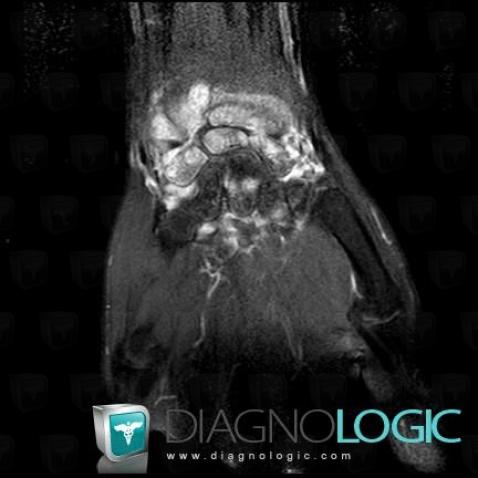

The images below illustrate this case for diagnoses Rheumatoid arthritis, for the modalities (MRI)

- Diagnosis Rheumatoid arthritis, Location(s) Other carpal bones, with gamuts Ulna - Distal part, with gamuts

- Diagnosis Rheumatoid arthritis, Location(s) Mediocarpal joint, with gamuts Radio/Ulno carpal joint, with gamuts

- Diagnosis Rheumatoid arthritis, Location(s) Other carpal bones, with gamuts Bone marrow edemaLunate, with gamuts Bone marrow edemaScaphoid, with gamuts Bone marrow edema

- Diagnosis Rheumatoid arthritis, Location(s) Other carpal bones, with gamuts Ulna - Distal part, with gamuts

- Diagnosis Rheumatoid arthritis, Location(s) Mediocarpal joint, with gamuts Radio/Ulno carpal joint, with gamuts

- Diagnosis Rheumatoid arthritis, Location(s) Other carpal bones, with gamuts Bone marrow edemaLunate, with gamuts Bone marrow edemaScaphoid, with gamuts Bone marrow edema